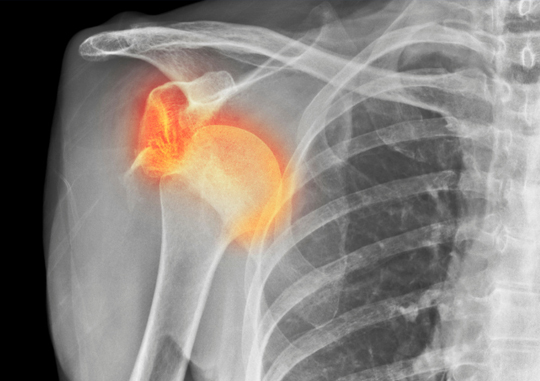

Shoulder Dislocation

Occurs when the upper arm bone (humerus) is forced out of the shoulder socket due to trauma or instability. It can be partial (subluxation) or complete.

• Icon Symptoms: Intense shoulder pain, visible deformity, swelling, and inability to move the arm

• Icon Treatment: Immediate reduction (repositioning), immobilization with a sling, physical therapy, and surgery for recurrent dislocations